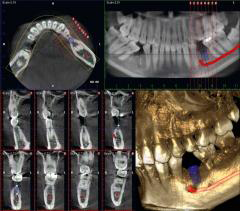

歯科用CTスキャン

従来のX線写真は2次元的な平面での診断しかできませんが、歯科用CTスキャンでは3次元の立体画像でのレベルに変わるのでより多くの情報が得られます。

歯科用CTスキャンはコンピュータを駆使したデータ処理と画像の再構成で、断層写真を得ることができる装置です。主に、インプラント治療、親知らずの抜歯、歯周病治療、根管歯内療法、矯正歯科などの治療に用いられます。

3次元の高画質画像を用いることで、断層方式パノラマX線写真やデンタルX線撮影法では判別できない、痛みや症状の原因の究明に役立ちます。

CTスキャンとインプラント治療

インプラント治療では、埋入する部位の術前の骨の状態(質や厚み、高さ、形態など)がX線レントゲンよりも正確に診査・診断ができるので、切開や剥離をしない手術や増骨術などに対しても判断が即日に行えます。

歯科用CTスキャンでの撮影画像をもとに的確な治療計画を立てることは、安心な治療への第一歩です。